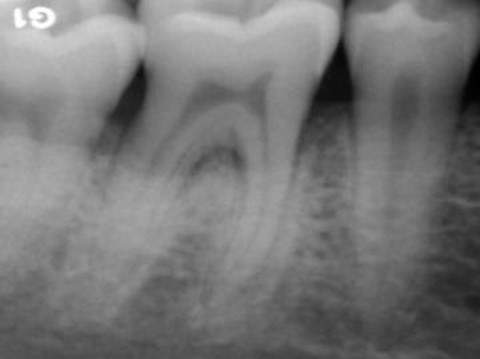

I mange tilfælde kan paradentose behandles med ikke-kirurgiske metoder, såsom ved at der opretholdes optimal mundhygiene og udføres tandrensning, hvor tændernes rødder også renses (tandrodsrens). Men når sygdommen er fremskreden med betydelig skade på tandkød og knoglevæv, kan kirurgisk behandling være nødvendig. Tandlægen vil typisk anbefale kirurgi, når der er vedvarende betændelse. Det gælder, når der er:

• dybe tandkødslommer, som forhindrer effektiv renholdelse.

• knogletab, som kræver genopbygning.

Operationen udføres for at reducere dybe tandkødslommer, hvor bakterier kan samle sig. Tandlægen lægger tandkødet til side for at fjerne plak og tandsten fra rødderne, hvorefter tandkødet sys tættere til tanden for at mindske lommens dybde og gøre det nemmere at holde området rent fremover.

Vævsregenerering og knogletransplantation

Denne teknik bruges til at stimulere genvækst af patientens egen knogle og støttevæv, der er blevet ødelagt af paradentose. Under operationen ilægges vækstfaktorer med eller uden knogle, hvilket stimulerer helingen af støttevævene til tanden.

Hvis paradentosen har forårsaget stort knogletab, kan en knogletransplantation være nødvendig for at genopbygge den mistede knoglemasse. Her han tandkirurgen bruge patientens egen knogle eller kunstig knogle. Målet er at stabilisere tanden og forbedre knoglens evne til at støtte tanden.